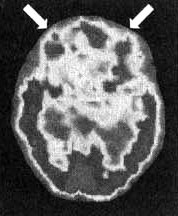

Результаты сканирования SPECT у Сэлли

Иллюстрация к книге — Измените свой мозг - изменится и жизнь! [i_001.jpg]

Снимок в горизонтальной плоскости — мозг в состоянии покоя. Обратите внимание на хороший уровень активности в префронтальной области (отмечено стрелками).